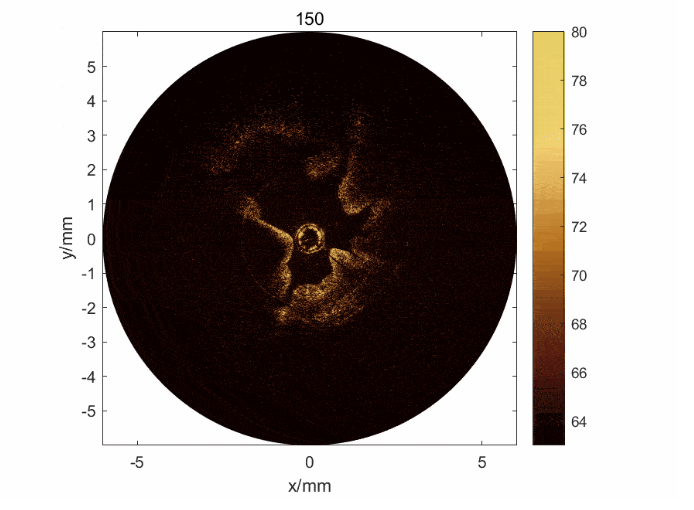

圖2: a) 子宮內(nèi)膜損傷模型兔的OCT/超聲圖像及其圖像分割和量化方法; b) 通過(guò)雙模態(tài)獲取的信息可以判斷子宮內(nèi)膜的損傷程度,驗(yàn)證了雙模態(tài)的必要性